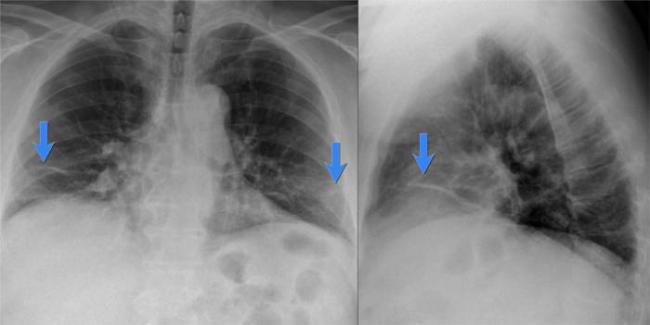

Помимо опроса и объективного осмотра, включающего перкуссию и аускультацию грудной клетки, проводят рентгенологическое исследование в двух положениях тела (в 2-х проекциях). Это основной метод обнаружения ателектазов легких.

На рентгеновских снимках выявляют следующие признаки, указывающие на спадение легочной ткани:

Однородное затемнение в области поражения. Размеры тени зависят от вида ателектаза: при долевом выявляется обширное затемнение, при сегментарном — в виде клина или треугольника, расположенного вершиной к корню легкого, дольковые ателектазы множественные и похожи на очаговую пневмонию. Дистензионный ателектаз расположен низко, около диафрагмы, имеет небольшие размеры и вид поперечных полос или темных дисков. Смещение органов: при компрессионном ателектазе смещение наблюдается в здоровую сторону, так как на стороне поражения давление больше, при обтурационном, наоборот – смещение будет в сторону ателектаза, так как на стороне поражения нарастает притягивающее отрицательное давление. Подъем купола диафрагмы – это видно по расположению печени.

Помимо всего перечисленного выше, рентгеноскопия, то есть исследование «вживую», позволяет увидеть куда смещаются органы в зависимости от фазы дыхания, кашля. Это является дополнительным признаком ателектаза, помогающим выявить тип болезни.

Предварительным, рентгенологическим диагнозом является «синдром правой доли», при котором выявляется затемнение площади средней доли правого легкого.

Частое возникновение ателектаза правого легкого связано с анатомическими особенностями правого среднедолевого бронха: он узкий и длинный, поэтому часто происходит его перекрытие при патологическом процессе.